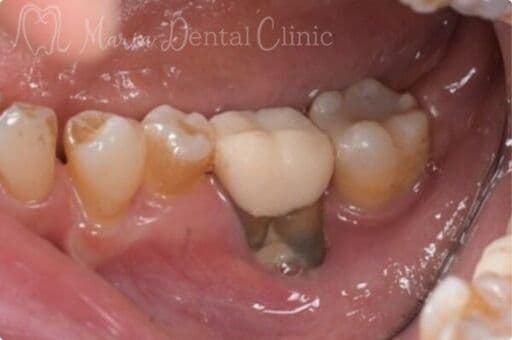

【症例】サイナスリフトで骨を増やし、奥歯の支えを回復したインプラント治療

本症例の患者様は、右側の歯を抜歯した後そのまま放置していたことで噛み合わせが大きく乱れ、右上の歯周病が進行して抜歯に至りました。抜歯後は上顎洞に近接して骨量が著しく不足していたため、サイナスリフトによって新たな骨を増やし、インプラントを支える土台を再建しました。十分な骨量を確保することで、奥歯の咬合支持を回復した症例です。

| 治療内容 | サイナスリフト、インプラント、矯正治療 |

|---|---|

| 治療期間 | 10ヶ月 |

| 治療回数 | 4回(他、抜糸、術後3ヶ月後、1年後の経過観察等を除く) |

| 治療費用 | 3,300,000円(税込、サイナスリフト他、矯正治療を含む) |